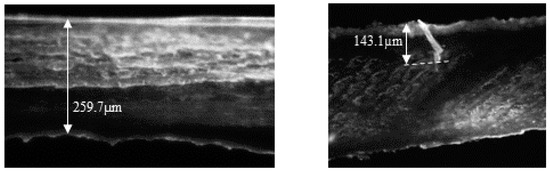

To assess the depth of the pores formed using the Hydra.needle™, three porated nails were cut in half and placed on a cryostat holder with the cut surface placed upwards. Blocking was performed in gel (Tissue-Tek® O.C.T.™ Compound by Sakura) after which the samples were frozen and cut in a cryostat (Leica CM1860UV, Leica Mycrosystems, Wetzlar, Germany) at −27 °C. Five nail serial cross sections were obtained from each nail with a thickness of 7 µm and mounted on microscopy slides. During these sequential nail sections, one nail section was collected and placed on microscopy slides, whereas the next two were discarded. This cycle was repeated 5 times until 5 samples from each nail were collected for imaging. On the same day, the samples were observed under a fluorescence microscope (Leica DMI4000 B, Germany) using a 20x objective. The nails were photomicrographed and the thickness of the nails and the depth of the pores, when found, were measured. Data were evaluated using ImageJ software (National Institutes of Health, version 1.41 NIH). Figure 2 shows representative transversal cuts of a non-porated nail, following hydration and sanding only, and of a microporated nail following hydration, filing, and microporation. When pores were found, their depth was always less than the total thickness of the plate. For example, in the specimens shown in Figure 2, the total nail thickness was 259.7 µm, and the pore depth was 143.1 µm, suggesting that the microporation procedure did not create channels throughout the whole plate.

Figure 2.

Microscopic transversal images: Left panel: a hydrated, filed, non-porated nail with a 259.7 µm thickness. Right panel: a hydrated, filed, and porated nail into which a 143.1 µm pore was created.

This work aimed to provide further insight on the potential of a microporation–formulation combination approach as a tool to improve the efficiency of topical therapies for onychomycosis. A proof-of-concept for this approach was provided in 2015 by Chiu et al. [22], who demonstrated the lateral diffusion of a marker across the nail plate from nanoparticle reservoirs immobilized in created pores; the nanoparticles were observed 70 µm deep into the nail. Further work combining microporation with tioconazole nanocapsules found that a single poration step enhanced delivery of the antifungal when combined with a single dose but not when followed by multiple doses of the nanocapsules [21]. Lastly, some work [37] testing dissolvable microneedle (circa 1000 µm depth × 500 µm middle dm × 700 µm external dm) array patches containing terbinafine and methylhydroxy-4-benzoate reported an extremely fast permeation across bovine hooves, comparable to that observed across a cellulosic filter membrane. However, the hooves had been soaked in 70% ethanol for 24 h prior to the studies, and the impact of this step on the poration effectiveness and permeation results is unclear. Prior work performed with human nail clippings [21,22] used a dermaroller (Infinite Beauty®) with 250 µm titanium needles, and given this “roller” poration action, trench-like structures or elongated cracks were created on the nail structure in addition to pores. Thus, a device (Figure 1) enabling a microporation action perpendicular with respect to the nail surface was used for this study, with the hope of creating channels that enter deeper into the nail structure. The Hydra.needleTM device with 0.6 mm long titanium needles was operated manually, and an approximate number of pores (~20) was created in the IVPT diffusion area (0.196 cm2), which corresponds to ~102 pores/cm2. The surface area of fingernail and toenail plates ranges between ~1.5 and 5.3 cm2 [38,39], so to recreate an equivalent pore density in practical applications, a nail poration device would need to create 153–540 pores across the whole nail plate, respectively. The microscopic images of porated nails (Figure 2) suggest that the pores created were less than 150 µm deep, suggesting that less than half of the length of the titanium needles penetrated the nail plate. While poration was effective in this study, there is no information with which the results reported here can be compared. Overall, there is very little information regarding the optimum depth and density of nail poration required for the treatment of onychomycosis, so this is an area requiring further research. Importantly, an antifungal must reach effective concentrations across the whole nail plate as well as at the nail bed. This is in contrast with skin poration, which aims to bypass the stratum corneum barrier to deliver drugs to the live skin layers. A successful approach will need to consider pore density as well as how much a specific drug can diffuse laterally from the pores into the surrounding plate structure.